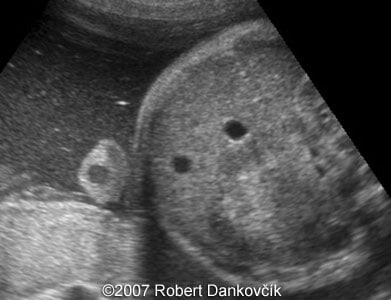

Images 1, 2: 2D sonography; 32 week of pregnancy; transverse planes through the fetal skull showing dilated third ventricle and dominant interhemispheric cyst extending to the right.

Images 3, 4: 2D sonography; 32 week of pregnancy; coronal planes through the fetal skull showing dilated lateral ventricles and interhemispheric cyst extending to the right.